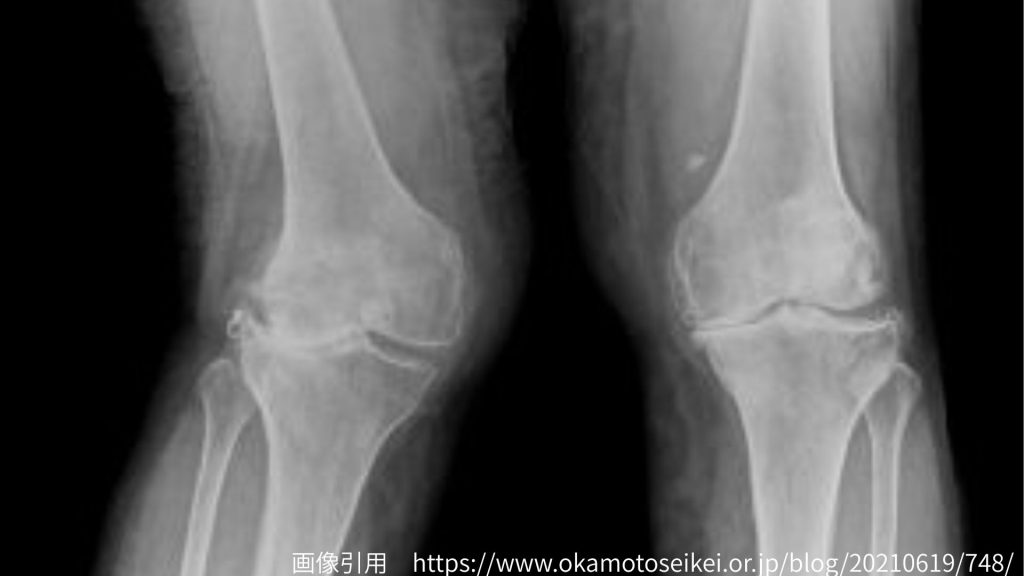

1.X脚が整体で変わらないケース ― 骨実質の変形 ―

成長期や外傷後などで、大腿骨や脛骨そのものの形に変形がある場合、骨格自体のアライメントが変わってしまっているため、整体だけでの矯正は難しくなります。

このようなケースでは、骨の構造に合わせて筋や関節の動きを整えるサポートを行うことで、痛みや歩行動作の安定を目指します。変形そのものを戻すのではなく、「機能的に動ける身体」に導くことが重要です。また、後述する軟部組織の問題が重複している場合(骨の変形+軟部組織の問題)が多いので、これらの問題を取り除くことでX脚は部分的な改善が期待できます。